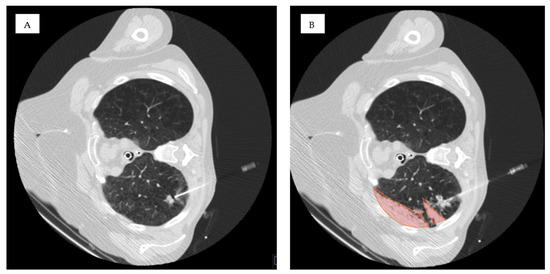

| Lesion location in D area | 53 | 46% | 34 | 40% | 19 | 63% | 0.034 * |

| Lesion location in D area | 1.402 | 0.517 | 7.369 | 1 | 0.007 * | 4.064 | 1.477 | 11.186 |